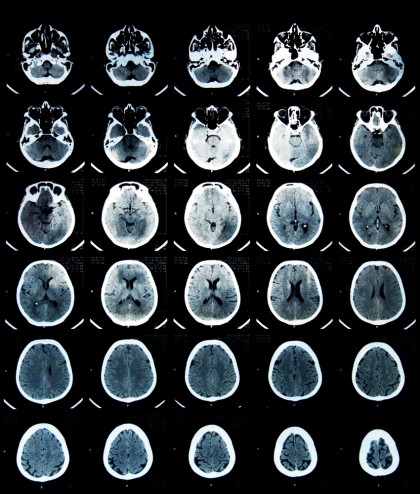

Acest algoritm foloseşte inteligenţa artificială pentru a recunoaşte semnalele demenţei cu aproximativ doi ani înainte ca boala să debuteze, pe baza scanării PET a unui singur amiloid, o proteină specifică de la nivelul creierului celor care au boala Alzheimer.

În lumea medicală se cunoaşte de mult timp faptul că se acumulează depozite de amiloid la nivelul creierului celor cu un declin cognitiv mediu, un deficit care a fost asociat cu demenţa. Însă chiar dacă această acumulare începe cu decenii înainte ca demenţa să se instaleze, această proteină nu a putut fi până acum folosită ca biomarker a demenţei, pentru că nu toţi pacienţii ajung în final să dezvolte boala.

În cercetarea de faţă, autorii au folosit datele oferite de un studiu global privind examinările clinice şi imagistice ale pacienţilor voluntari, pe baza acestora dezvoltând algoritmul de predicţie, care a dovedit o precizie de 84% a algoritmului înainte de apariţia simptomelor.